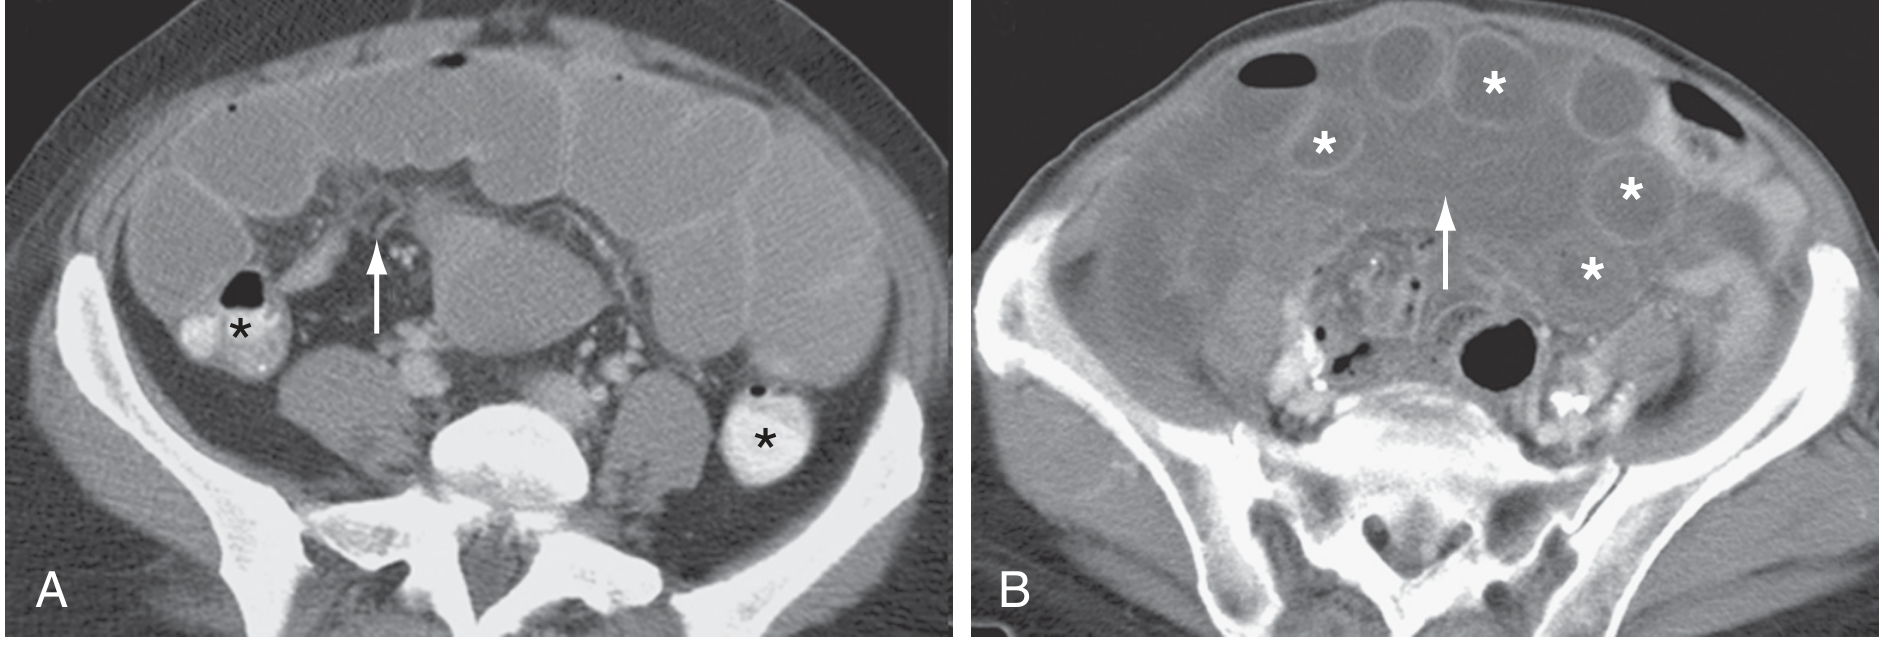

CT images: Simple SBO (A) and Closed-loop SBO (B)

Axial CT: Panel A shows simple SBO with dilated proximal small bowel loops () and transition zone (arrow); Panel B shows closed-loop SBO with multiple fluid-filled dilated loops () and central twisted mesentery (arrow)